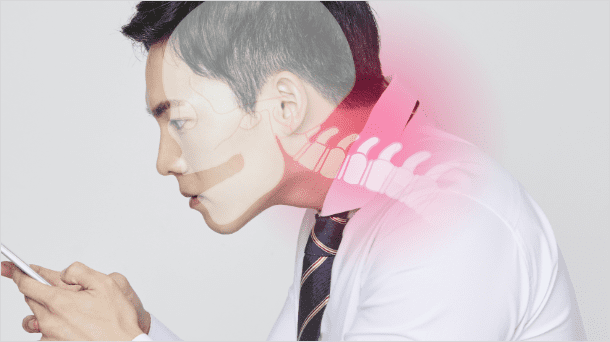

- 원인

오랜 시간 고개를 숙이고 스마트폰을 사용하는 경우